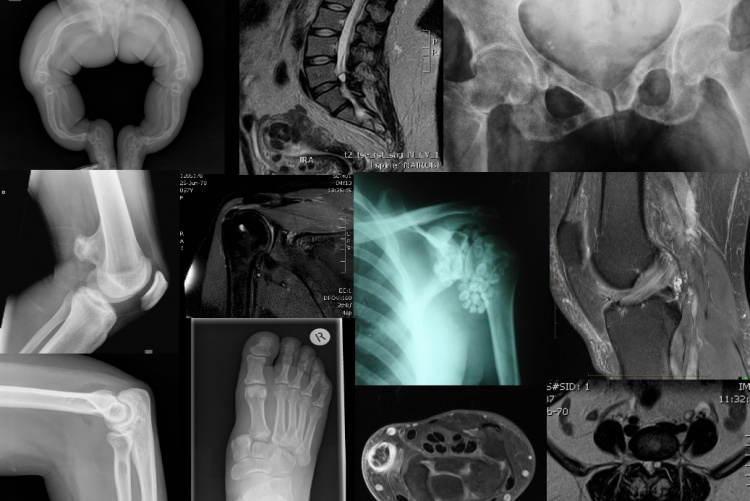

DIAGNOSTIC IMAGING AND RADIATION MEDICINE

We have four main programmes in the Department; a Master of Medicine in Diagnostic Radiology, Master of Medicine in Radiation Oncology, Higher diploma course in Medical Diagnostic Ultrasound and Fellowship in Interventional Radiology. We also have PhD programme in Radiology. Our programmes are interactive, problem-based, multi-disciplinary and student-centered to enable our students to achieve the highest levels of competence.